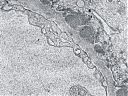

Elektronenmikroskopie

Abb. 18: Elektronenmikroskopische Veränderungen der glomerulären Basalmembran

Die Lichtmikroskopie (HE oder PAS) zeigt eine diffuse, gleichmäßige Verdickung der glomerulären Basalmembran. Die Basalmembran nimmt das Aussehen eines dicken eosinophilen Bandes an. Mit diesen Färbungen kann man aber die Ursache der Basalmembranverdickung nicht erkennen (d.h. die Unterscheidung zwischen einer Verdickung aufgrund der Ablagerung von Immunkomplexen oder einer gesteigerten Produktion der Basalmembranmatrix ist nicht möglich). Diese Veränderungen können jedoch in einer Silber-Methenamin Färbung oder elektronenmikroskopisch dargestellt werden. Mit diesen Techniken wird die Basalmembranmatrix angefärbt, jedoch nicht die Immunkomplexe. Mit dieser Färbetechnik wurden charakteristische ultrastrukturelle Veränderungen in der Basalmembran von Ehrenreich und Churg beschrieben. Die erste Phase ist die Bildung von subepithelialen Immunkomplexen, danach folgt die Synthese neuer Basalmembransubstanzen, die sie einschließen und schließlich werden die Immunkomplexe abgebaut und sind nicht mehr nachweisbar.

Klassifikation der membranösen Glomerulopathie nach Ehrenreich und Churg:

Stadium Elektronenmikroskopischer Befund

I Subepitheliale elektronendichte Ablagerungen

II Subepitheliale elektronendichte Ablagerungen mit dazwischenliegenden Basalmembran (Spikes)

III Einbeziehung der subepithelialen elektronendichte Ablagerungen in der Basalmembran

IV Reabsorption der Ablagerungen mit Verlust der elektronendichten Ablagerungen und Aufhellung der Basalmembran.